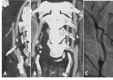

Fig. (16)

Vasculitis is big mimicker of dissection. On the other hand, vasculitis the one of causes of dissection. In a patient with Behcet’s disease, there is brain stem infarction (A) and intimal flap type dissection of arcus aorta (B) and bilateral CCAs (C, D) on CTA. All lumens in dissected arcus aorta is filling (B). Both two lumens in the right CCA is filling while filling lumen (true lumen) is very thin and other (false lumen) is is thrombosed in the left CCA (C, D). In another patient with osteogenesis imperfecta type 1, there is infarction within the left ACA territory (E) with focal narrowing and dialation (string and pearl sign) of left A2 on the volume rendering CTA (F), consisting with dissection of proximal part of left A2. In another patient with Behcet’s disease, vessel wall irregularities with saccular dilatations (pseudoaneurysms) are seen along the both ICAs and right VA (H). Pseudoaneurysm of the celiac trunk is seen in the same patient (I).